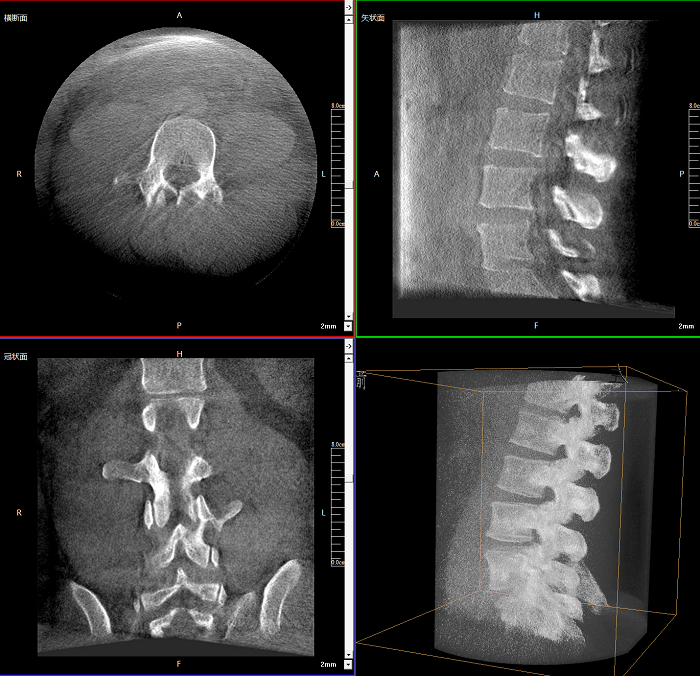

三维成像 全面观察

任意视角、任意切面观察

术中实时生成横断面、矢状面、冠状面及三维影像,可在任意切面、任意角度评估植入物和解剖结构的相对位置。

术中CT检查 减少翻修概率

通过术中三维影像的检查,可以立即发现植入物的错位,减少不必要的第二次手术,减少并发症概率以及感染风险。

Clinical picture

临床图片